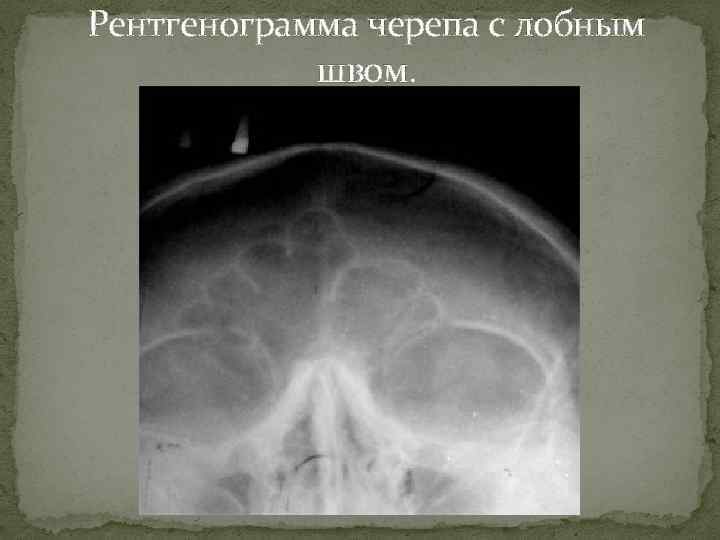

Рентгенография небного шва: Медицинские исследования и диагностика